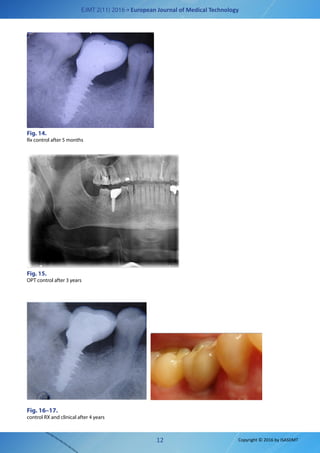

Fig. 14.

Rx control after 5 months

OPT control after 3 years

Fig. 16–17.

control RX and clinical after 4 years

At the end of the osseous-integrative process,

crown and annually monitored. (Fig 14-17)